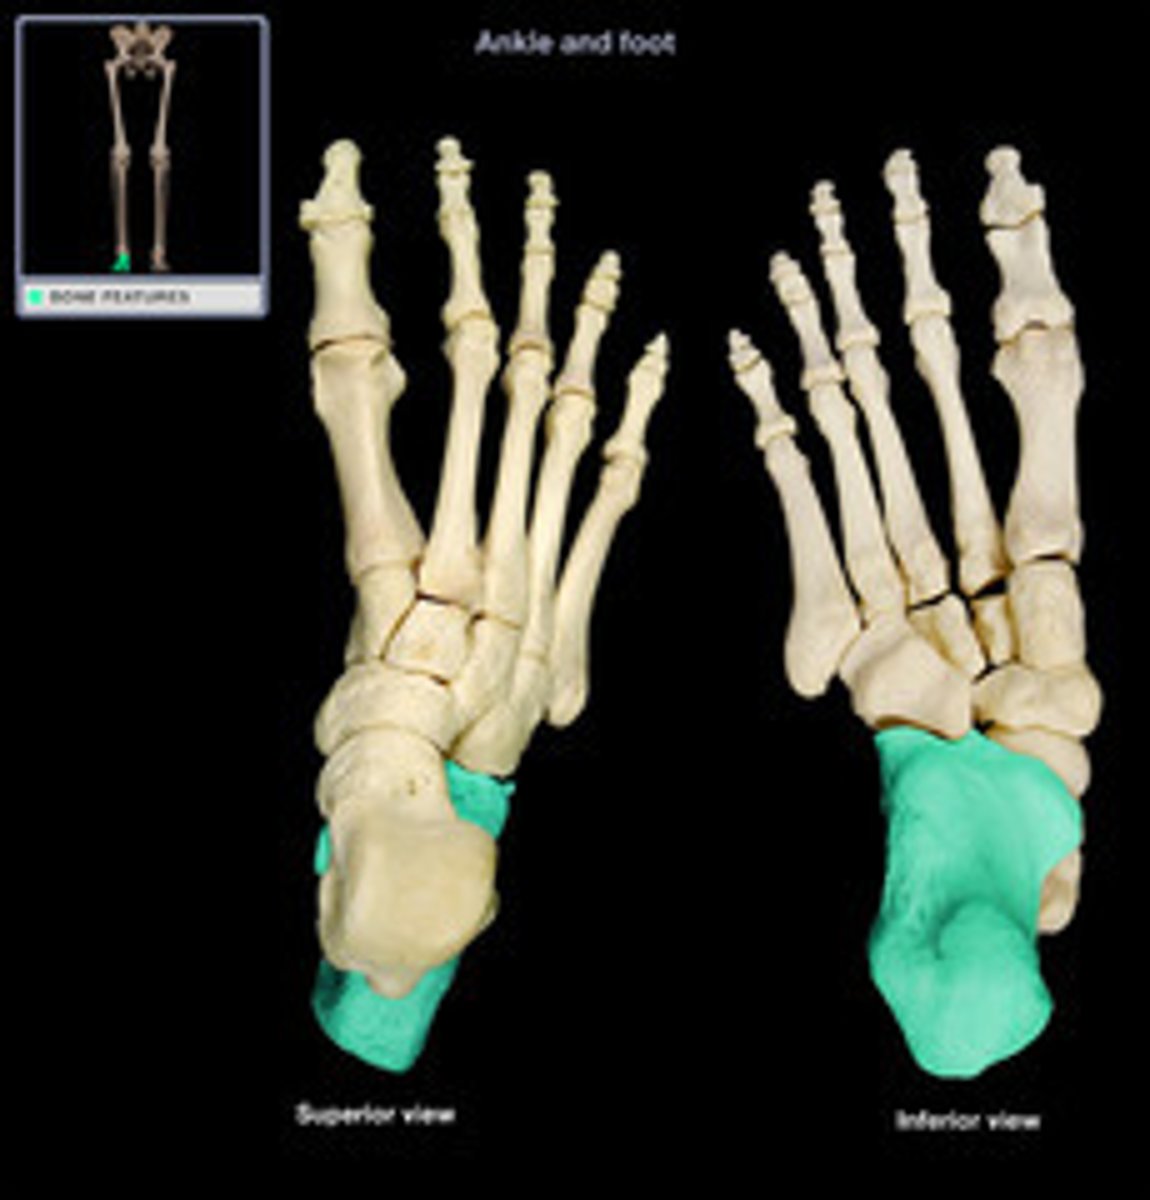

Tarsal Bones

What is the term of the bones highlighted in blue?

Calcaneus

What is the term of the bones highlighted in green?

Talus

What is the term of the bones highlighted in pink?

Navicular

Medial Cuneiform

Intermediate Cuneiform

Lateral Cuneiform

Cuboid

Metatarsals

Phalanges of the Foot

Proximal Phalanges of the Foot

Middle Phalanges of the Foot

Distal Phalanges of the Foot

What is the term of the bones highlighted in red?